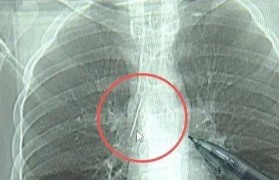

17岁小伙参军体检发现胸腔内有根5cm缝衣针,父母回忆或是1岁时扎入,取出时已锈迹斑斑

近日,安徽17岁小伙小陆参加征兵体检,胸片结果显示:胸腔内有一处金属高密度影,形态细长,像一根针。...